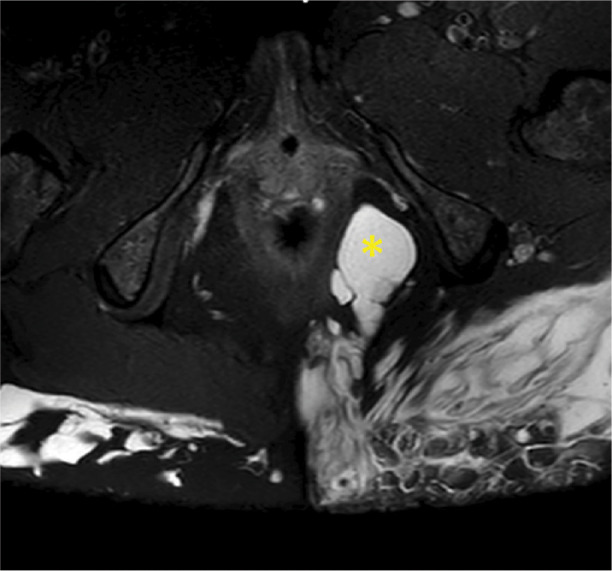

Teaching point: To highlight the potential complications associated with AQUAfilling injections, emphasizing the importance of early detection and proper management.

Abstract Image